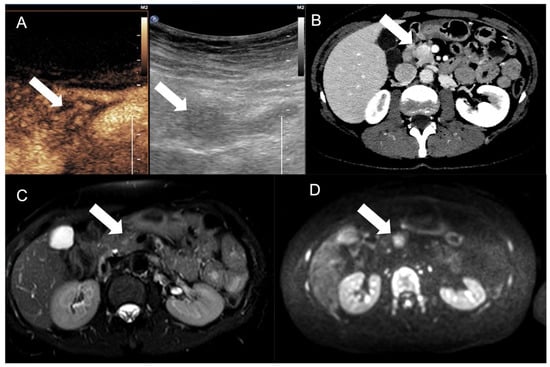

2.3.3. Ultrasonography and Contrast-Enhanced Ultrasound (CEUS)

3.2. Liver Metastases